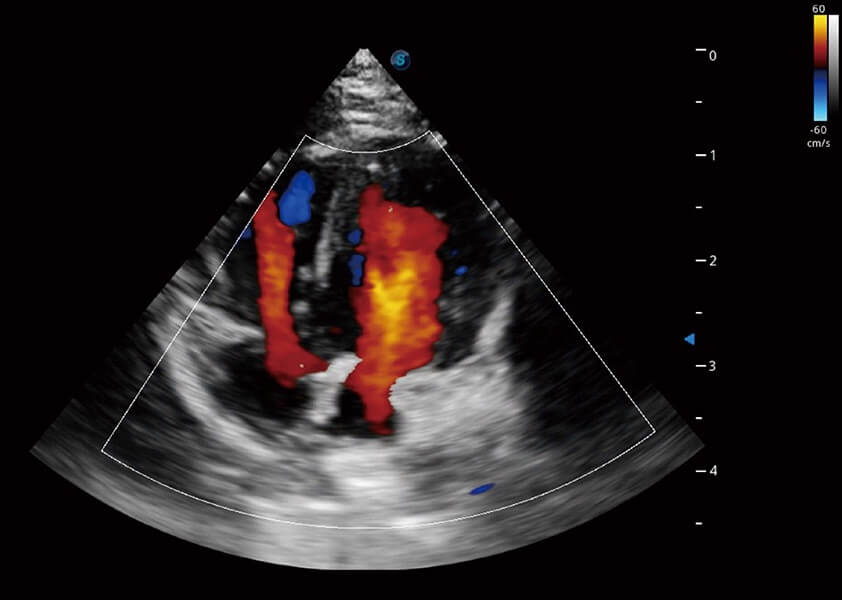

ProPet 60 作为一款高端台式动物超声设备,为动物医生的日常诊断提供了一系列贴合动物临床需求、解决临床实际问题的高级成像功能。凭借全系列高清探头,满足医生对腹部、心脏、生殖、浅表、肌骨等成像的所有需求,切实帮助您提升检查效率,提高诊断信心。

兽用彩色多普勒超声诊断系统

动物是人类最亲密的朋友和最值得信赖的伙伴。环球UG官网也一直致力于探索动物专用的超声影像解决方案。 全新推出的ProPet系列,是环球UG官网在动物超声影像智能化、专业化、精准化的一次跨越式革新。动物不能用言语来表述自己的不适,通过超声影像,ProPet系列搭建了动物医生与不同物种沟通的“桥梁”,为动物医生注入了“治愈之力”。